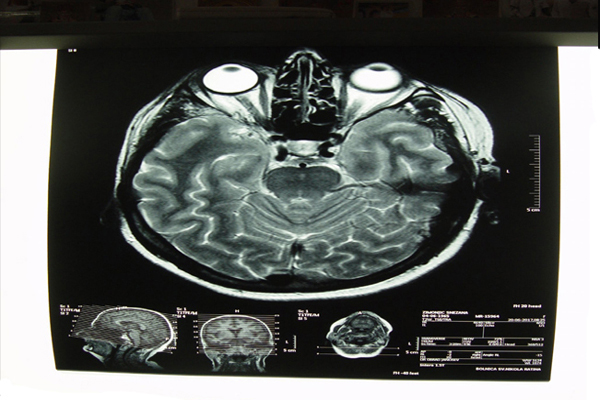

Hirurški tretman bolesti mozga, kičmene moždine i perifernih nerava. Nakon prethodne dijagnostike, a u savremeno doba nejčešće MR dijagnostike, potreban je pregled neurohirurga radi daljeg planiranja lečenja.